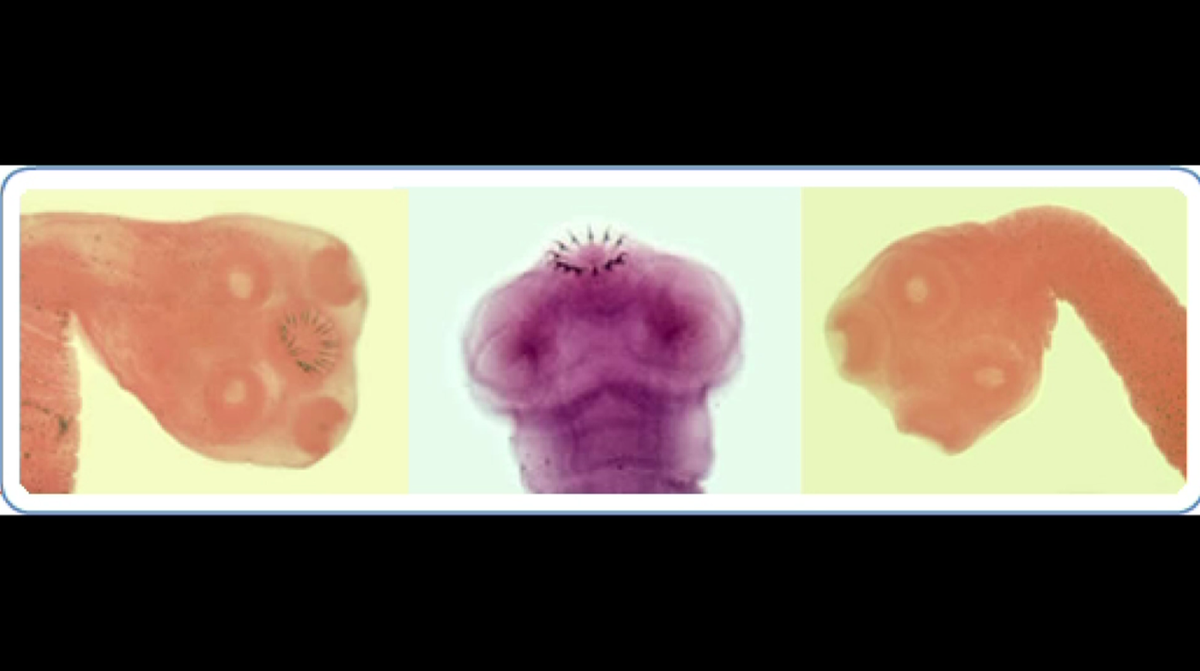

Surgeons remove live parasite from man's brain after he has "worst headache of his life" http://cbsn.ws/1QcK9sL pic.twitter.com/FlkQ9Cp1ze

@CBSNews, "The CDC says there are about 1,000 hospitalizations in the U.S. each year for brain infections caused by the pork tapeworm."